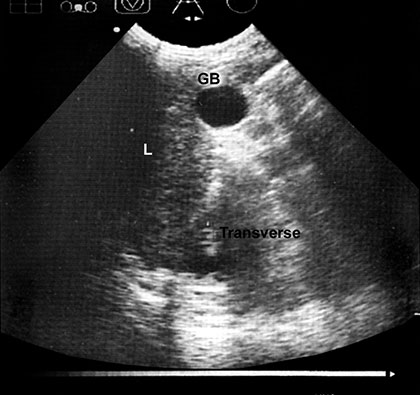

Structure of differing acoustic impedance (such as gall-bladder and liver) are much easier to distinguish from one another than structure of similar acoustic texture (e.g. liver and kidney) (Fig. 1.10).

If acoustic densities are vastly different, sound beam is completely reflected and total acoustic shadowing occurs.

Acoustic shadowing is observed behind bone (ribs), stones in kidney or the gallbladder and air (intestinal gas).

Echoes are not detected if no difference in acoustic densities are encountered. Homogenous fluid (urine and cyst content, but also ascites and pleural effusion) are seen as echo free (black) structure, e.g. gallbladder and hepatic vessels (Fig. 1.11).

Fig. 1.10: Transverse section of liver, gallbladder and right kidney are shown in the subcostal view